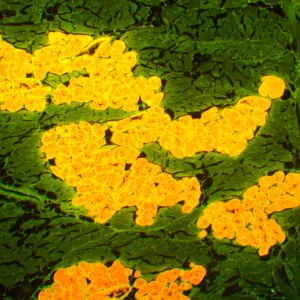

Микроскоп MAGUS Lum 450L – это модель, на которой можно проводить исследования как в светлом поле, так и в свете люминесценции, а при доукомплектовании микроскопа дополнительными компонентами станут доступны и исследования по темному полю, фазовому контрасту или в поляризованном свете. При исследованиях в свете люминесценции MAGUS Lum 450L освещает препарат синим или зеленым цветом – объекты, соответственно, производят зелено-желтый или красный свет. Люминесцентные микроскопы применяются в медицинских экспертизах, криминалистических или фармакологических исследованиях, в работе ветеринарного контроля и санэпиднадзора. Эта модель оснащена системой «умного» освещения, подстраивающей интенсивность света под характеристики объектива, и ЖК-экраном, на котором можно контролировать параметры работы.

- Для работы в свете люминесценции препарат освещается синим или зеленым светом и производит желто-зеленый или красный